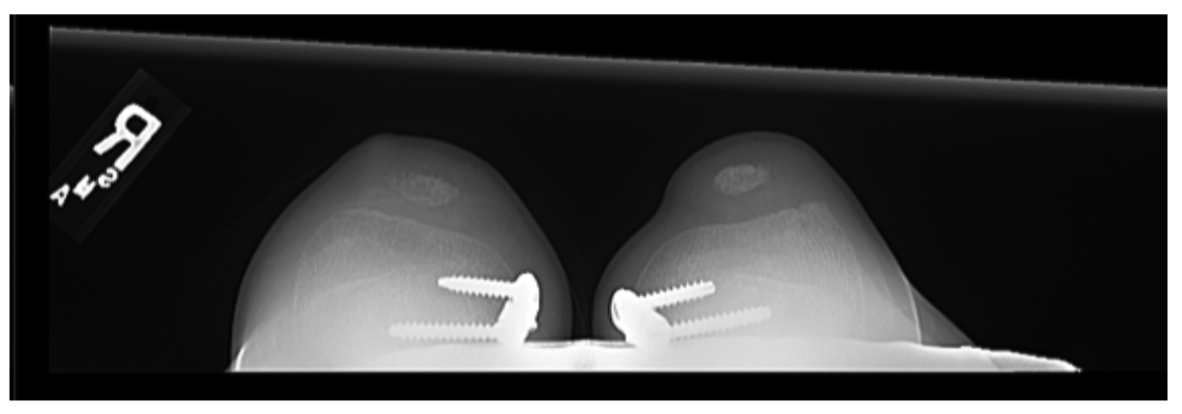

In surgery, a pathologic attachment of the iliotibial band to the patella was noted and released. The patient underwent removal of bilateral hinge knee plates 10 months postoperatively (Fig. 3), at which time he was doing well and reported no pain.

Figure 3: 3 month postoperative merchant view X-ray of the patient’s knees.